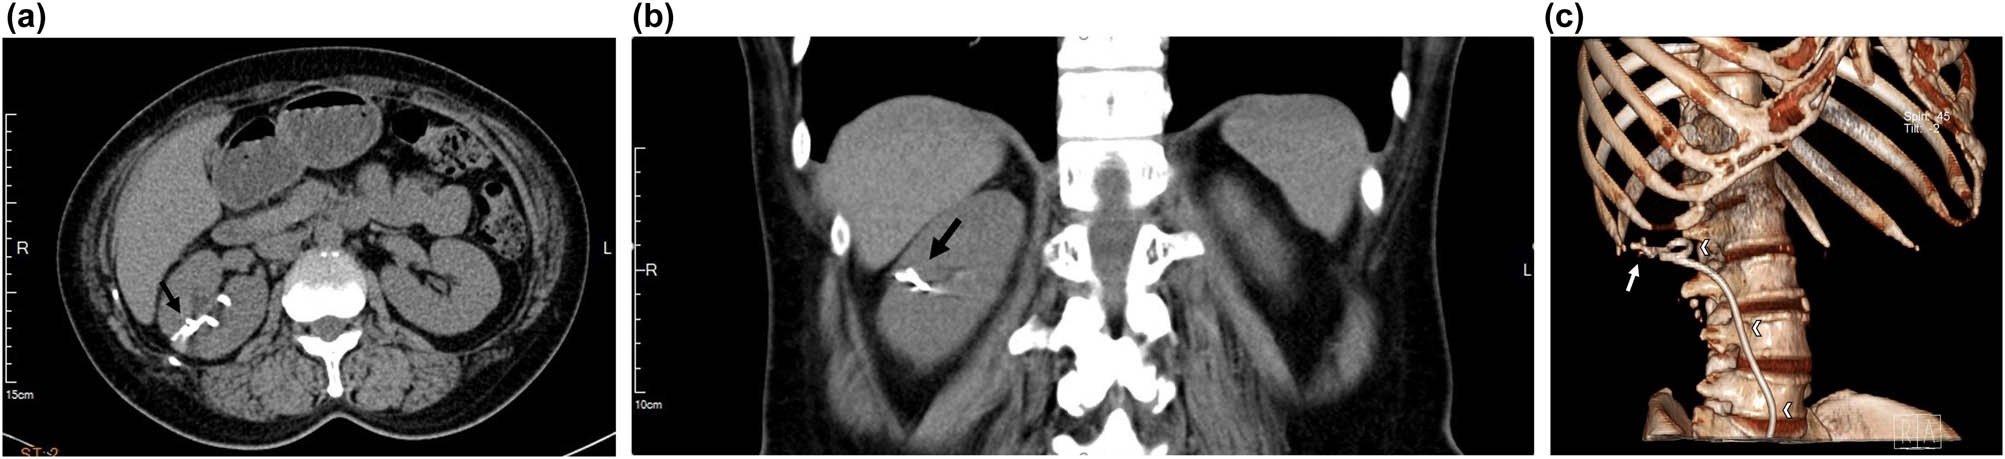

A plain radiograph of the kidneys, ureters, and bladder (KUB) showed a new radiopaque lesion in the right renal shadow compared with the pre-PCND plain film (Figure 1). This artifact was considered to be a retained ruptured guidewire or fragments of the PCND. Further CT imaging was performed to determine the precise anatomical location and the radiodensity of the object, which was revealed to be a curvilinear hyperdense coil within the upper pole parenchyma of the right kidney (Figure 2a–c). The radiologists judged that the coil could be the remnants of a guidewire used during the PCND procedure.

Computed tomography image of the intrarenal foreign body (arrow) and its relationship with right double J ureter stent (arrowheads). (a) Transverse cut, (b) coronal cut, and (c) reconstruction.